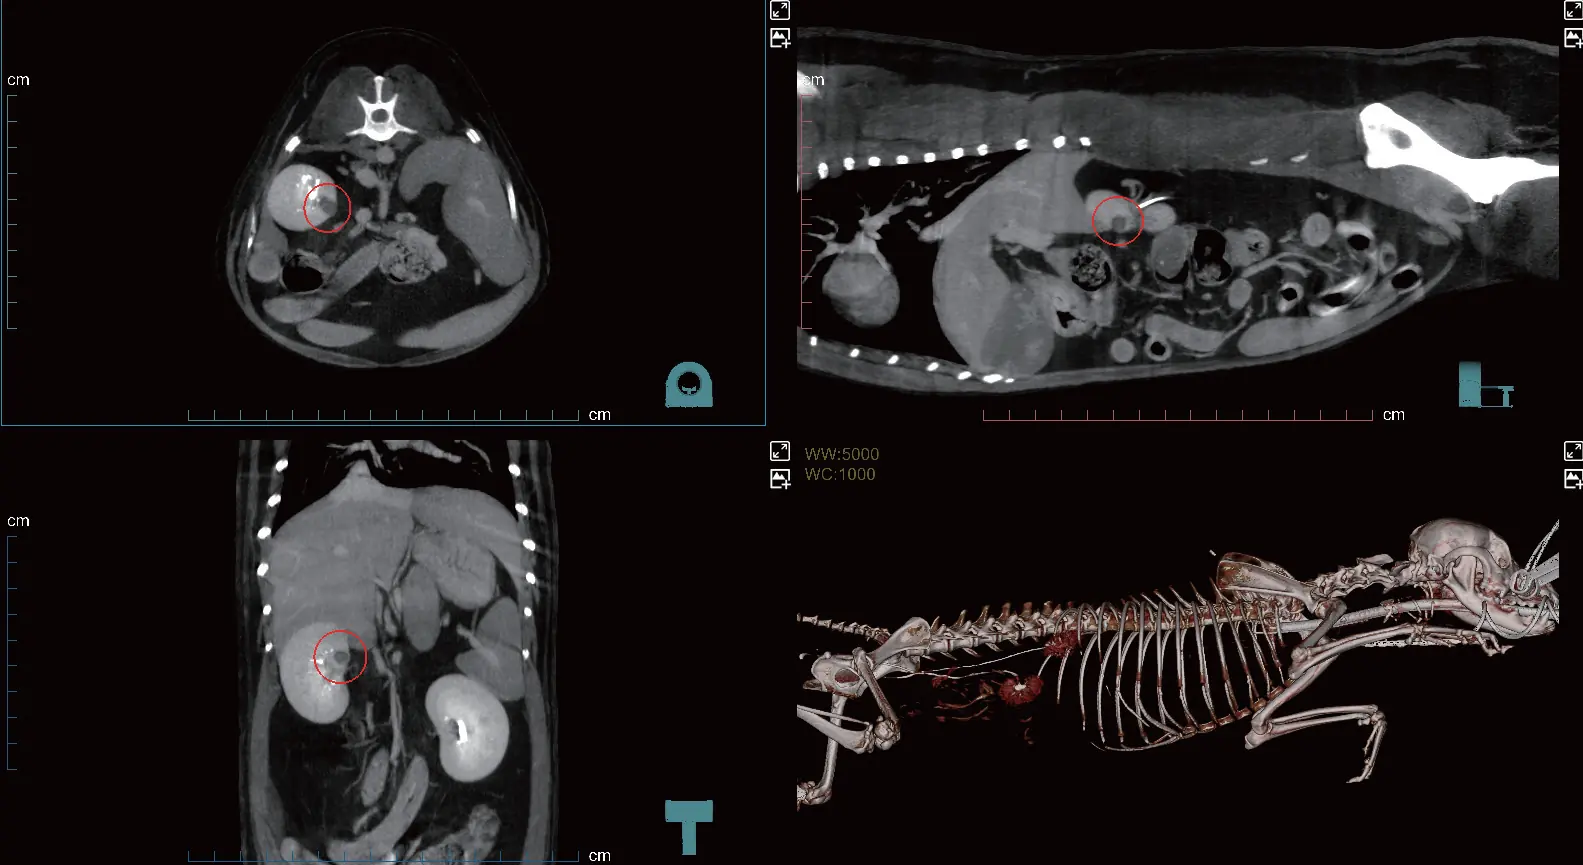

Simetrik prostat büyümesi ile birlikte homojen kontrastlanma. Halka şeklinde kontrastlanan çok sayıda kistik yapı. Büyümüş internal ve eksternal iliak lenf düğümleri.

Arteriyel, venöz ve geç fazları tek bir taramada otomatik olarak kaydeder. İş akışını kolaylaştırır ve fazlar arası karşılaştırmaya imkân tanıyarak lezyonların daha net ve verimli şekilde saptanmasını sağlar.